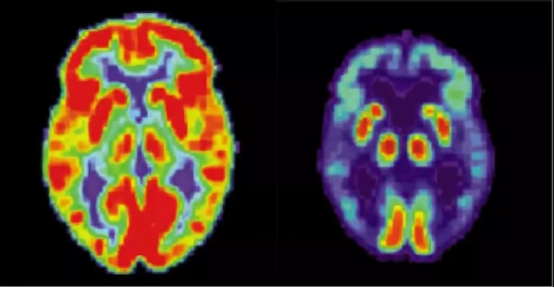

"我们正在建设专用输注中心。"北京天坛医院副院长透露,首批20家三甲医院将开展用药培训,需进行PET确认淀粉样蛋白沉积的患者才能用药。